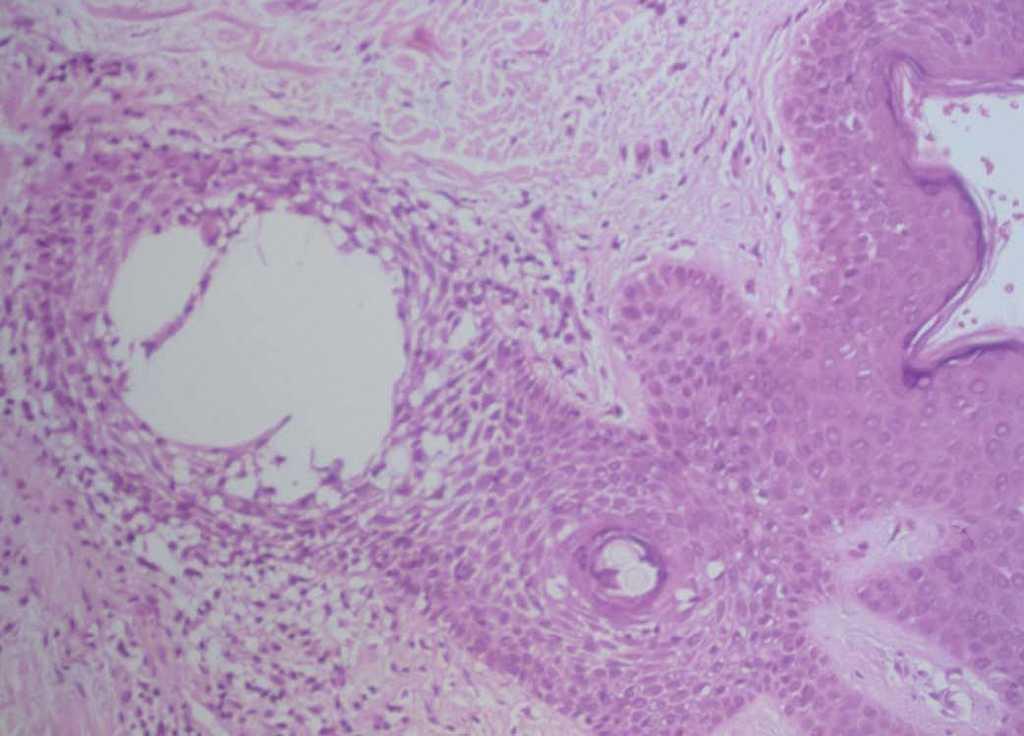

Se practicó una biopsia cutánea que mostró una epidermis normal sin alteraciones de la membrana basal. Destacaban infiltrados linfocitarios de predominio perifolicular y grandes espacios quísticos con pérdida de la conexión entre los queratinocitos foliculares (fig. 2). La tinción con hierro coloidal mostró depósitos de mucina en estos espacios quísticos (fig. 3). Se realizaron las siguientes exploraciones complementarias con resultados normales y/o negativos: inmunofluorescencia directa de piel afectada, recuento, fórmula y bioquímica sanguínea básicas, hormonas tiroideas, anticuerpos antinucleares, anti-ADN, anti-Ro y anti-La.

Fig. 2.—Infiltrado linfocitario perifolicular con grandes espacios quísticos con pérdida de conexión entre los queratinocitos foliculares. (Hematoxilina-eosina, ×100.)